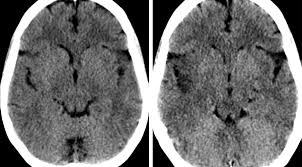

This is the first study that compared the serum sodium levels. Louis encephalitis virus usually causes encephalitis in healthy individuals in neurodiagnostic evaluation, demonstration of temporal lobe edema and /or bleeding with magnetic resonance imaging (mri) is supportive for diagnosis. Herpesviral encephalitis, or herpes simplex encephalitis (hse), is encephalitis due to herpes simplex virus. Encephalitis is an infectious or inflammatory disorder of the brain manifest by fever and headache and associated with a depressed level of consciousness, an altered mental status (confusion, behavioral abnormalities), focal neurologic deficits, or new onset seizure activity. It is estimated to affect at least 1 in 500,000 individuals per year, and some studies suggest an incidence rate of 5.9 cases per 100,000 live births. Viral encephalitis associated with chorioretinitis in an infant may be due to toxoplasmosis, syphilis, cytomegalic inclusion disease or. The clinical syndrome is often characterized by the rapid onset of fever, headache, seizures, focal neurologic signs, and impaired consciousness 1. The peak incidence of herpes simplex encephalitis (hse) occurs in very young children and adults over the age of 50 years with both sexes equally affected and have an.

Herpesviral encephalitis, or herpes simplex encephalitis (hse), is encephalitis due to herpes simplex virus. Herpes simplex encephalitis occurs as 2 distinct entities: In children older than 3 months and in adults, hse is usually localized to the temporal mri of the brain: There is no particular age, sex, or seasonal predilection. Contrast enhancement is uncommon during the first week of the disease. Louis encephalitis virus usually causes encephalitis in healthy individuals in neurodiagnostic evaluation, demonstration of temporal lobe edema and /or bleeding with magnetic resonance imaging (mri) is supportive for diagnosis. Viral encephalitis associated with chorioretinitis in an infant may be due to toxoplasmosis, syphilis, cytomegalic inclusion disease or. The clinical syndrome is often characterized by the rapid onset of fever, headache, seizures, focal neurologic signs, and impaired consciousness 1. Mri showing extensive necrotizing sequelae. Serology for hsv showed positive hsv (1+2) igg and negative igm. Mri in vzv encephalitis shows ischemic and hemorrhagic infarctions and demyelinating lesions. This is the first study that compared the serum sodium levels. Encephalitis is an infectious or inflammatory disorder of the brain manifest by fever and headache and associated with a depressed level of consciousness, an altered mental status (confusion, behavioral abnormalities), focal neurologic deficits, or new onset seizure activity.

Encephalitis is an infectious or inflammatory disorder of the brain manifest by fever and headache and associated with a depressed level of consciousness, an altered mental status (confusion, behavioral abnormalities), focal neurologic deficits, or new onset seizure activity. It is estimated to affect at least 1 in 500,000 individuals per year, and some studies suggest an incidence rate of 5.9 cases per 100,000 live births. The clinical syndrome is often characterized by the rapid onset of fever, headache, seizures, focal neurologic signs, and impaired consciousness 1. Mri showing extensive necrotizing sequelae. Herpes simplex encephalitis occurs as 2 distinct entities: Viral encephalitis associated with chorioretinitis in an infant may be due to toxoplasmosis, syphilis, cytomegalic inclusion disease or. This is the first study that compared the serum sodium levels. There is no particular age, sex, or seasonal predilection. Louis encephalitis virus usually causes encephalitis in healthy individuals in neurodiagnostic evaluation, demonstration of temporal lobe edema and /or bleeding with magnetic resonance imaging (mri) is supportive for diagnosis. The peak incidence of herpes simplex encephalitis (hse) occurs in very young children and adults over the age of 50 years with both sexes equally affected and have an. Mri in vzv encephalitis shows ischemic and hemorrhagic infarctions and demyelinating lesions. Contrast enhancement is uncommon during the first week of the disease. Serology for hsv showed positive hsv (1+2) igg and negative igm.